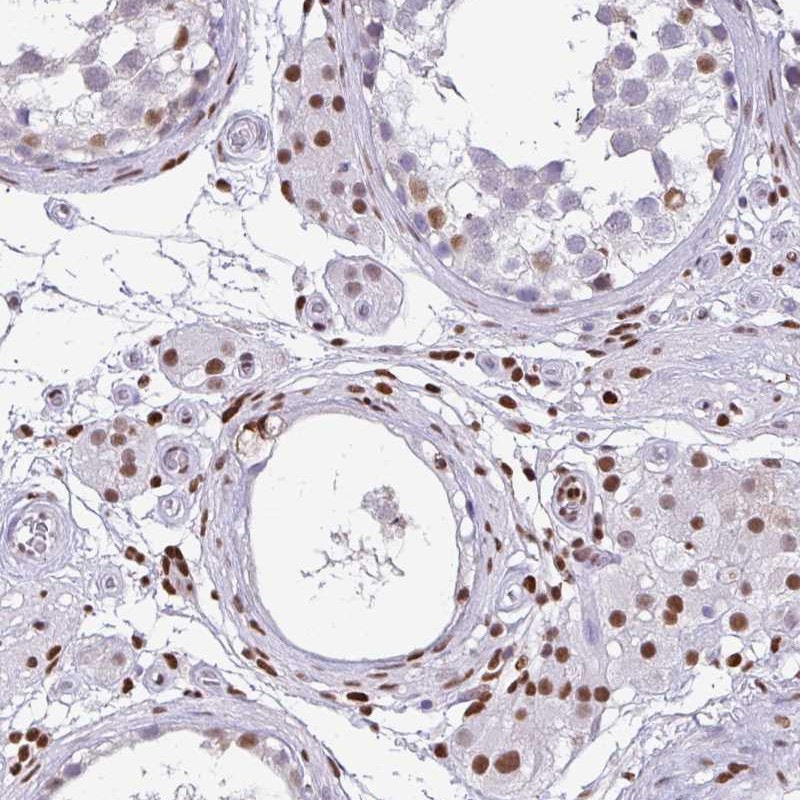

Immunohistochemical staining of human testis shows moderate nuclear positivity in cells in seminiferus ducts and Leydig cells.